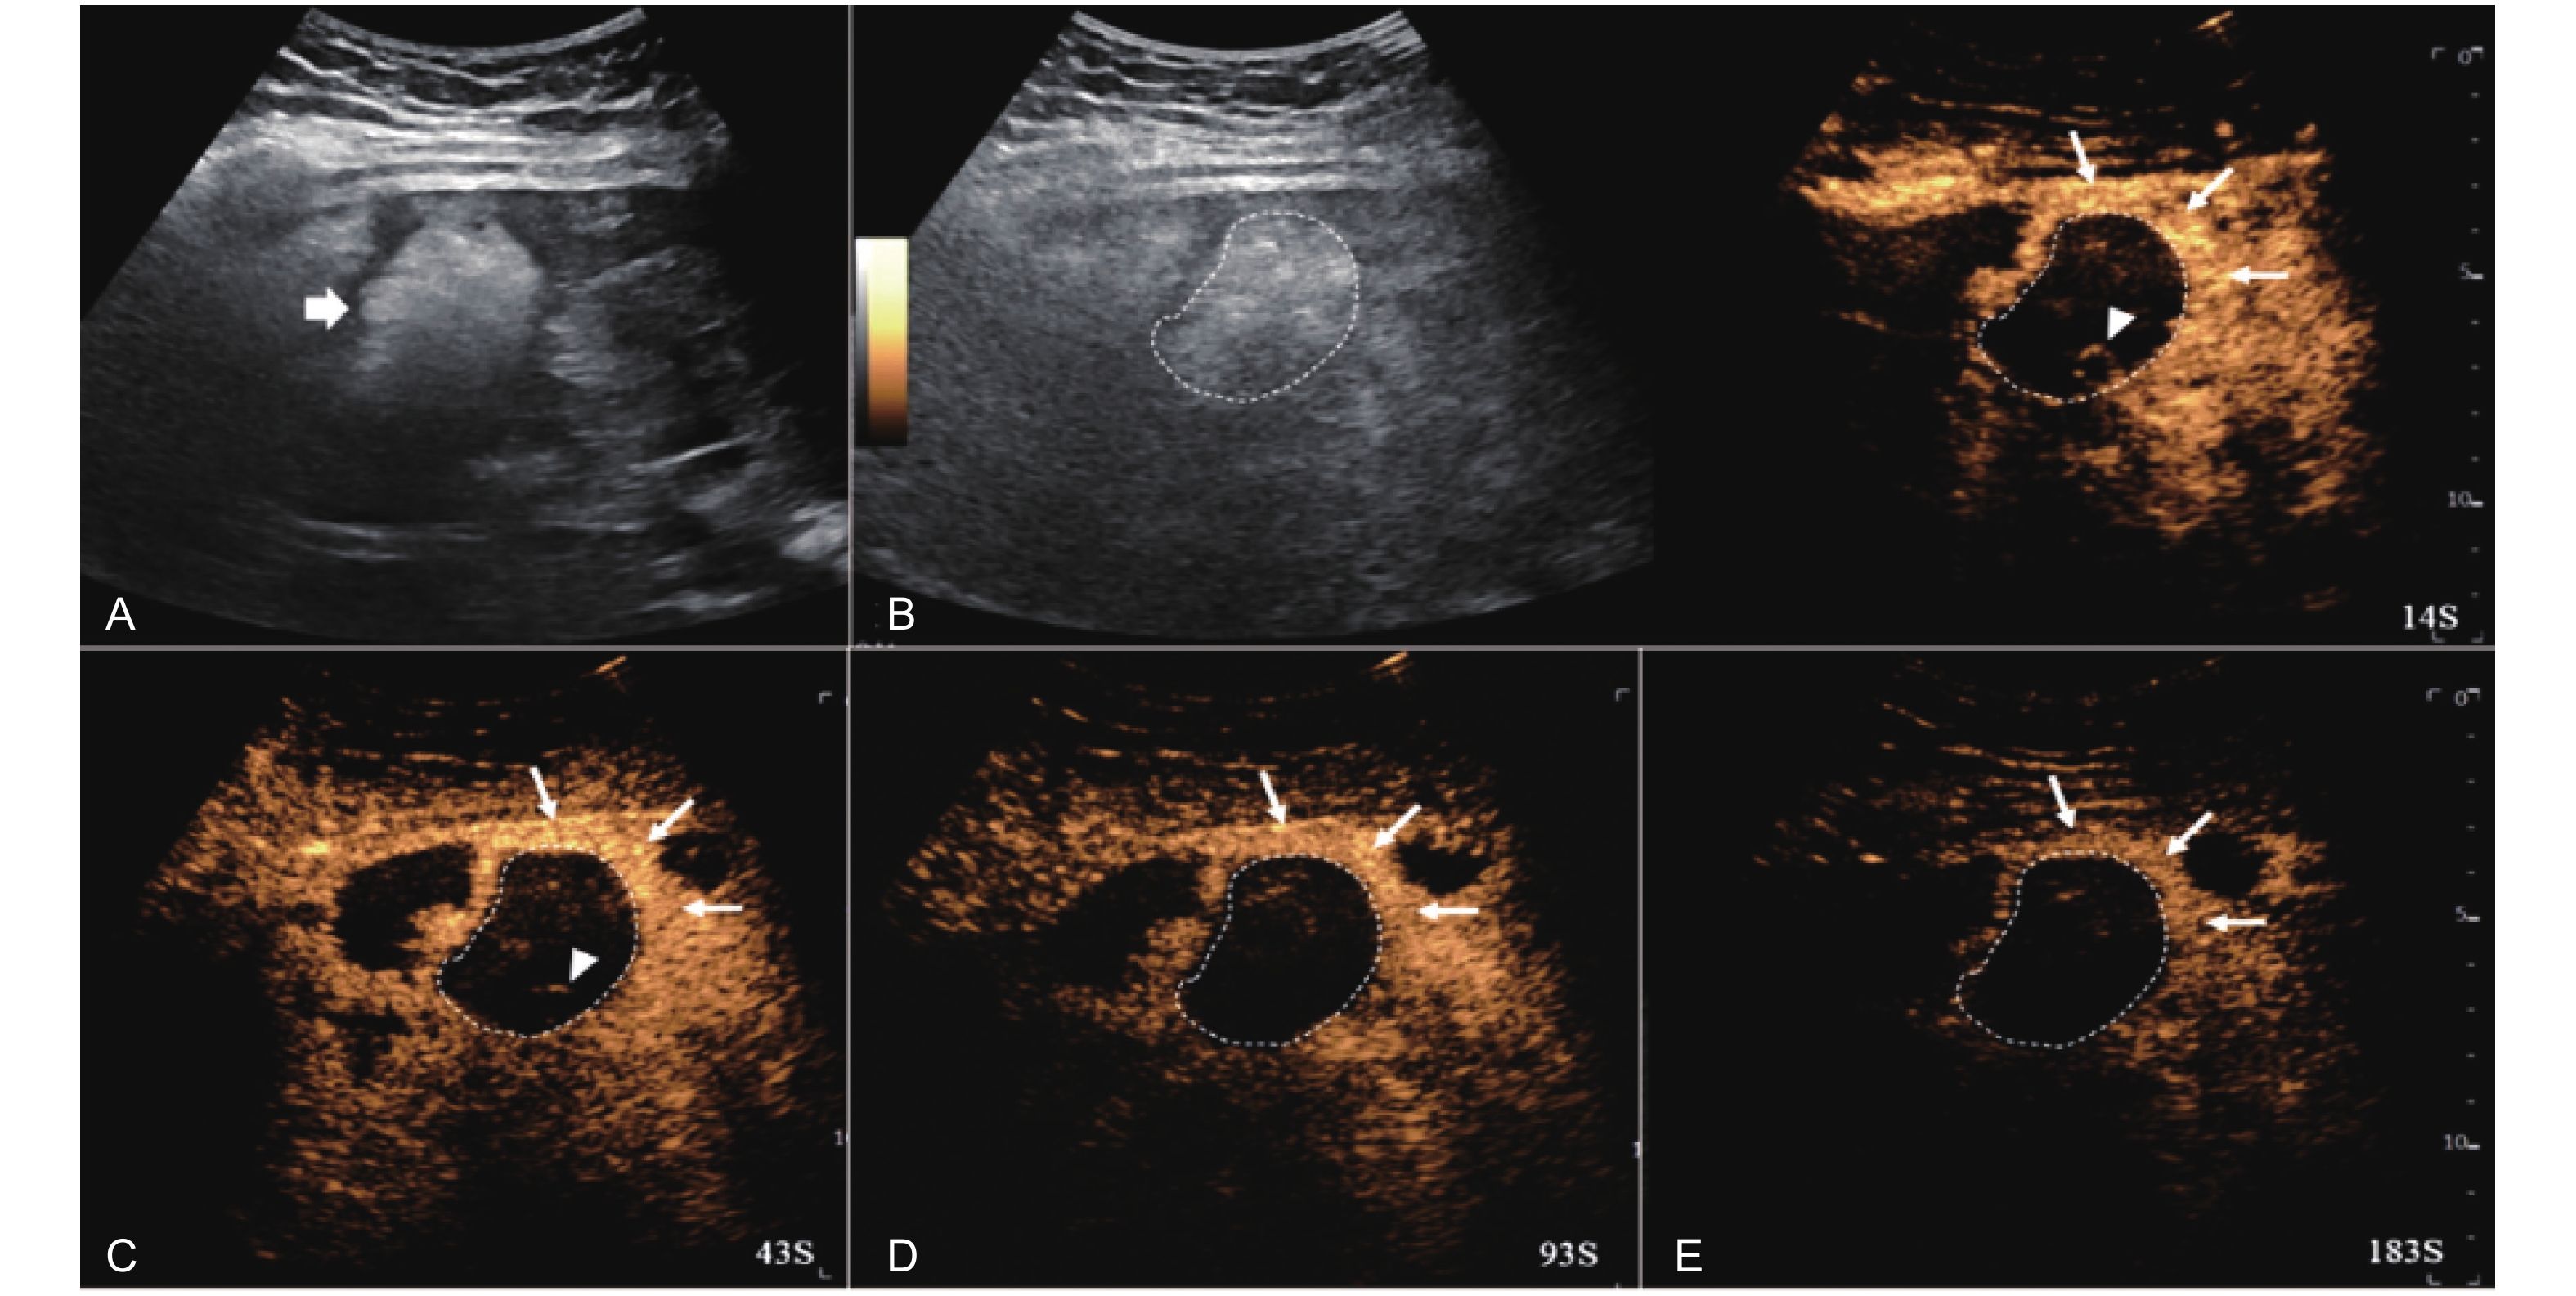

Figure 12

LR-TR Viable. Example of a treated tumor 55 days after TACE. (A) B-mode image shows a hypoechoic lesion (thick arrow) with well-defined margins, measuring 52 mm in segment III; (B) CEUS shows intralesional hyperenhancement with nodular protrusions along the margin (arrowhead) and perilesional hyperenhancement (thin arrow) during the arterial phase; (C-D) The lesion shows intralesional (arrowhead) and perilesional isoenhancement (thin arrow) without washout in the portal venous and late phases. Findings are consistent with LR-TR Viable."